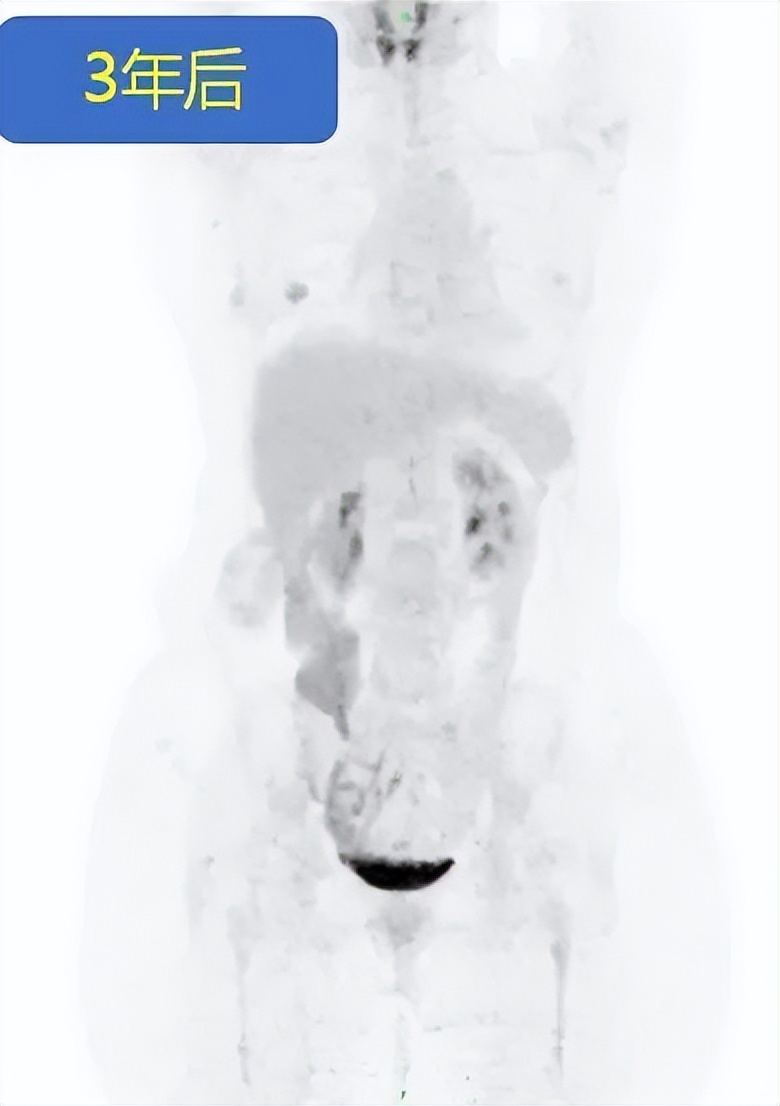

△PD-1抗体治疗结束1年后,PET-CT评价肿瘤仍为完全缓解

2021年7月,张女士停药满一年。医生分析认为,肿瘤再复发的可能性已经很小了。保险起见,张女士进行PET-CT检查,结果显示原肿瘤病灶代谢未见异常(图4所示),疗效评价仍为完全缓解。

基于此,2022年3月,袁龙主任医师为张女士进行了结肠造瘘还纳术。手术进行得非常顺利,张女士摆脱了随身携带的粪袋,回归了正常生活。